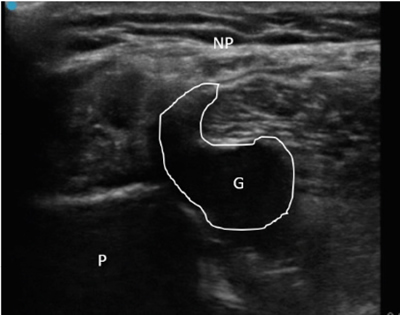

Ante estos hallazgos se decidió realizar ecografía clínica, objetivándose datos de neuropatía del nervio peroneo común (nervio engrosado, hipoecogénico y con pérdida del patrón fibrilar previo a su entrada en el túnel osteofibroso peroneo) coincidiendo con la compresión de una estructura compatible con un ganglión originado en la articulación tibio-peronea proximal. En ecografía dinámica, ante maniobras de flexo-extensión de pie, se objetivó un ascenso del ganglión y un mayor contacto con el nervio peroneo (Figura 1) a nivel de la zona de afectación neural. El paciente presentaba además un claro tinel ecográfico positivo a la compresión nerviosa y dolor a la ecopalpación del ganglión.

Fig. 1. Ecografía de corte axial del nervio peroneo común con características de neuropatía por compresión de ganglión. P: peroné. G: ganglión, resaltado perímetro para mejor visualización. NP: nervio peroneo común, que se encuentra engrosado, hipoecogénico y con pérdida del patrón fibrilar.